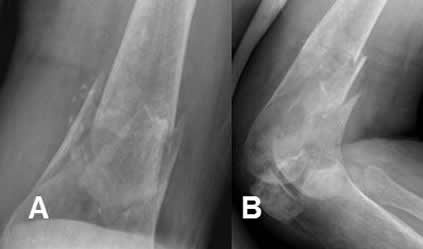

Fig 61. Fractura patológica.

A: Rx AP. Alteración en la densidad de la cabeza del húmero, con matriz condroide, por la presencia de encondroma. Se aprecia fractura transversa y no desplazada a nivel del cuello.

B: Rx AP. Imagen ovalada y radiolúcida en la diáfisis humeral, compatible con quiste simple. Existe fractura asociada, no desplazada y en sentido oblicuo.